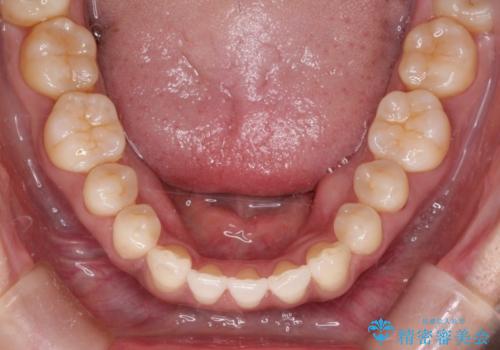

- 上顎の前歯のがたつきと、下の前歯の隙間を主訴に来院されました。

下の前歯が先天的に欠損していました。

上顎の歯と歯の間をわずかに削りスペースを作り、ガタガタの改善し、下顎の前歯は隙間を閉じる計画としました。

非常に協力的な患者様でしたので、早期に治療が終了することができました。